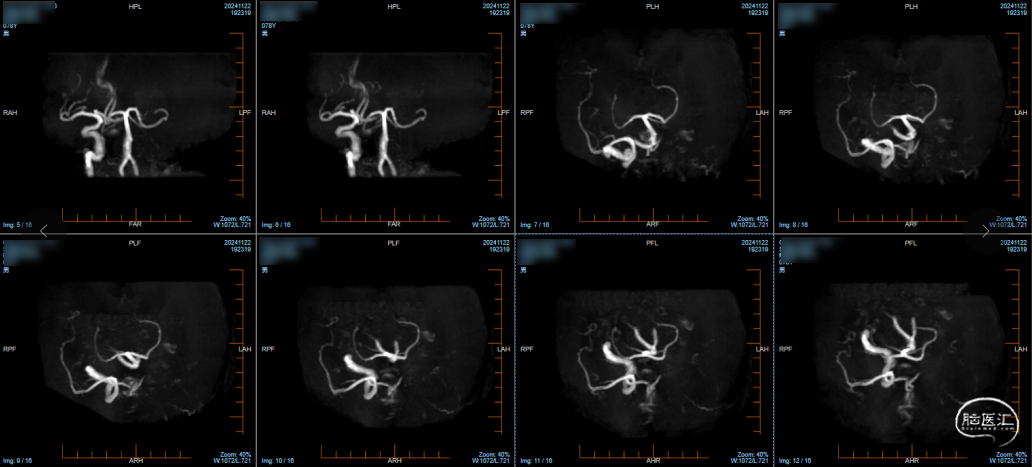

2024.11.22 颅脑MRA